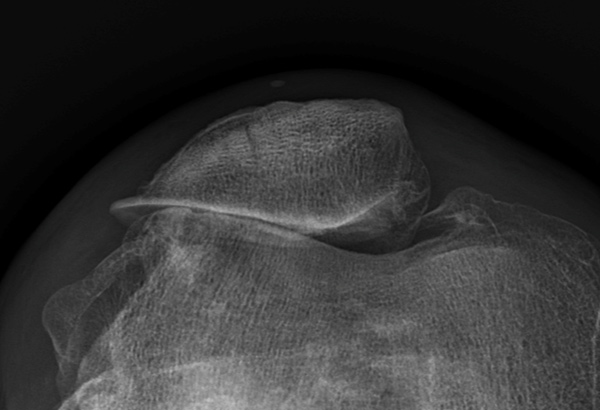

The first cases of quadriceps malalignment were identified serendipitously while measuring three-dimensional scans looking for variations in boney alignment. We identified several cases in which the alignment of the quadriceps tendon was severely malaligned. After analyzing 110 scans of patients with normal knees we were able to identify a huge range in the coronal and axial alignment of the proximal quadriceps tendon.

We looked closely at quadriceps alignment in two groups of patients – one with severe lateral patella osteoarthritis and one without. The group with lateral patella OA had much more externally rotated (lateralised) proximal quadriceps tendon. This fits with the hypothesis that malalignment of the quadriceps muscle and tendon is causing increased pressure on the lateral side of the patellofemoral joint resulting in the development of osteoarthritis. This challenges some of the current assumptions regarding the development of patella osteoarthritis, particularly the role of trochlear dysplasia (here are recent letters written regarding this controversy).

It is not just a malalignment of the quadriceps tendon – though measuring the quadriceps tendon alignment is a reliable surrogate for quadriceps muscle deformity. The muscle deformity can best be described by a rotation of the proximal muscle relative to the femoral shaft and knee joint. The range of rotational malalignment is at least 75 degrees. There are clear differences in the relative shape and alignment of the four components in of the quadriceps. It is also not caused by wasting of the vastus medialis components – which was actually 15% larger in patients with laterally rotated quadriceps. This challenges the long-held belief that patella maltracking is caused by weakness of the VMO – instead it appears to be a rotational malalignment of the entire quads.